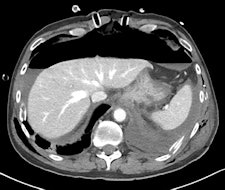

A full clinical evaluation of the patient is essential, and information about the etiology of the pseudoaneurysm, hemodynamic stability, and anticoagulation therapy is important. Studying the characteristics of the pseudoaneurysm is important, including anatomical localization, the size of the pseudoaneurysm sac, size of surrounding hematoma, diameter of pseudoaneurysm neck, vascular territory (superficial or deep/visceral) that the pseudoaneurysm arises from, and the type of end artery (expendable or inexpendable) in which the pseudoaneurysm is located. Ultrasound and CT angiography can determine all these features, although conventional angiography is used most of the time as a prelude to endoluminal treatment of the pseudoaneurysm, they stated.

radiopaedia.org/cases/gastroduodenal-artery-pseudoaneurysm.

A false aneurysm -- another term for a pseudoaneurysm -- is when there is a breach in the vessel wall such that blood leaks through the wall but is contained by the adventitia or surrounding perivascular soft tissue, according to Dr. Yuranga Weerakkody and Dr. Donna D'Souza et al, writing on radiopaedia.org. A direct communication of blood flow exists between the vessel lumen and the aneurysm lumen through the hole in the vessel wall. The risk of rupture is higher than that of a true aneurysm of comparable size due to poor support of the aneurysm wall, and thus false aneurysms generally require treatment.